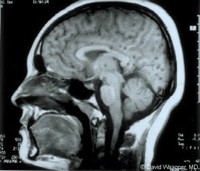

+Chụp cắt lớp vi tính (CT Scanner) não tìm các hình ảnh đặc hiệu (các nang sán là những nốt dịch có chấm mờ, kích thước 3-5mm, đôi khi nang có kích thước lớn đến 10mm, rải rác có nốt dạng vôi hóa);